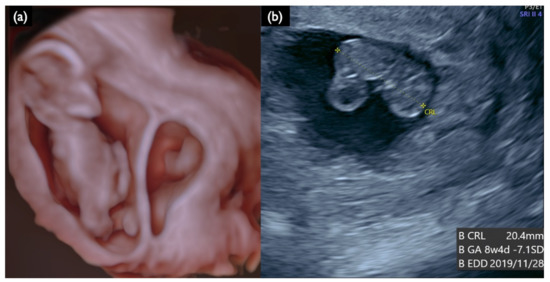

| FN1 | 47,XY,+21 | T21 negative | 1.07 | – | – | – | – | – | – | – | – | 46,XX | unclear | + | 7.2 | Increased NT, GE mild, NB defect, Lowset ear, TR mild, Small stomach, DV reverse, Tachycardia, T21 is strongly suspected |